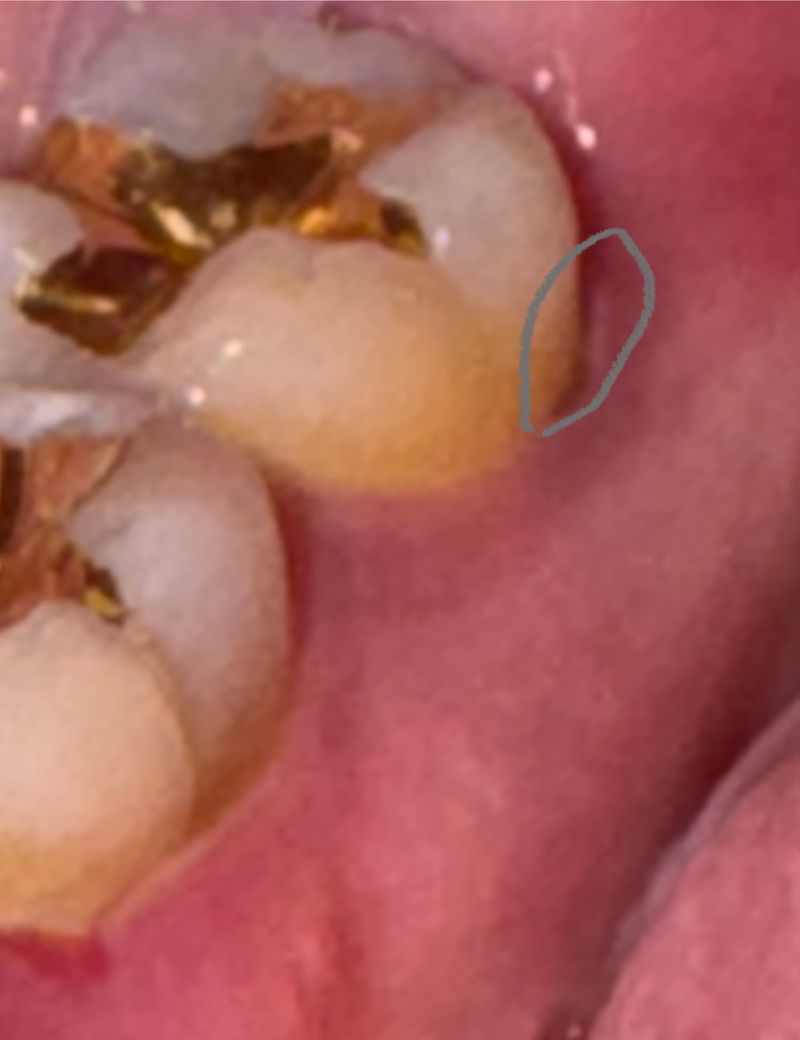

치아어금니에 검은줄?같이 되잇는데요

아래치아 끝에 어금니 안쪽 부분에 사진속 동그라미만큼의

검은줄? 연필로 쭉 그은거 같은게 보이는데요

충치일까요? 사진이 흐리긴한데요 변색?일수도 잇나여?

• 1번 째 사진

사진으로만 봤을 경우에는 약간 어두운 부분이 보이긴 하지만 빛이 비추지 않아서 그런 것일 수 있습니다. 크게 문제가 되진 않을 것으로 생각되나. 해당 부위가 불편하거나 걱정이 되신다면 치과의사 진료를 받아보는 것을 권유드립니다.

사진이 흐려서 얼핏 보기에는 그냥 그림자같은데, 치석일 수도 있을 것 같아요. 충치는 아닌 것 같아보이는데 직접 보고 긁어봐야 정확히 알 수 있어서 사진만 보고서는 확답을 드리기가 어렵습니다.

치아 착색일수도 있지만 퇴축한 잇몸으로 인해 어둡게 비쳐 보이는것 같습니다. 건강하세요.

실제로 봐야 정확히 알 수 있겠으나 단순 음영일 가능성이 높아보이고, 그게 아니면 착색 및 치석 같습니다. 충치 가능성은 낮아보입니다.